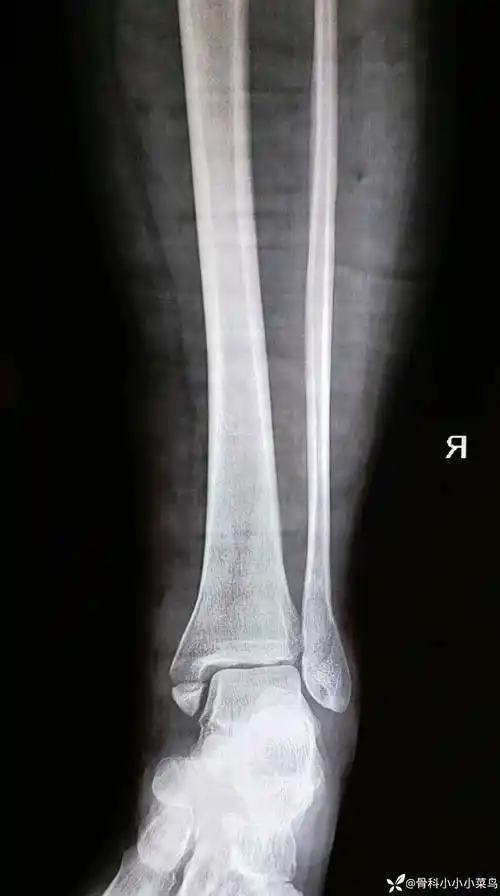

医生眼里:诊断很明确,踝关节的三踝骨折,骨折线累及内踝,外踝及后踝

外踝 后踝骨折